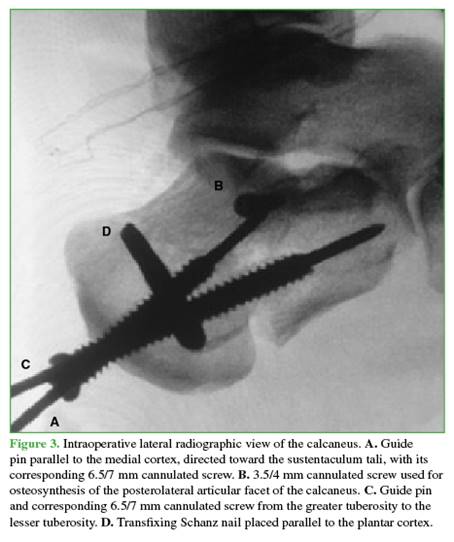

A transfixing Schanz nail is placed in the greater calcaneal tuberosity from lateral to medial, marking the entry point on the profile view, proximal to the plantar cortex. The Schanz nail is oriented perpendicular to the greater tuberosity, and its parallelism to the plantar cortex is assessed in the axial projection (Figure 1A).

The first assistant proceeds to perform traction using the transfixing Schanz nail to correct the deformity. Axial and varus/valgus traction is applied to restore calcaneal anatomy by ligamentotaxis. A first guide pin (for a 6.5/7 mm positioning screw) is then placed parallel to the medial cortex to attach the greater tuberosity to the sustentacular fragment—an anatomical component that is generally stable and undisplaced (Figure 1B).

STA is then performed, and the PLAF is reduced under direct visualization (Figure 2).

The PLAF is fixed with one or two pins, placed from lateral and posterior to anterior and medial, directed toward the sustentaculum tali. These are subsequently replaced with 3.5/4 mm cannulated compression screws (Figure 1C). Finally, the second guide pin (line C) is placed and replaced by a 6.5/7 mm full-thread cannulated screw. This screw runs parallel to the lateral cortex and supports the greater tuberosity with the lesser tuberosity (Figures 1D and 3).

The number and orientation of the 6.5/7 mm screws will depend on the fracture lines. The objective of these screws is to support the greater tuberosity with the calcaneal body and the lesser tuberosity, also creating a “scaf-folding” that provides stability to the posterolateral articular facet (Figures 4-6).